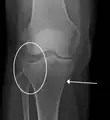

Fractura de meseta tibial leve en vista con Rayos X AP en la rodilla

Una fractura de meseta tibial vista con rayos-X